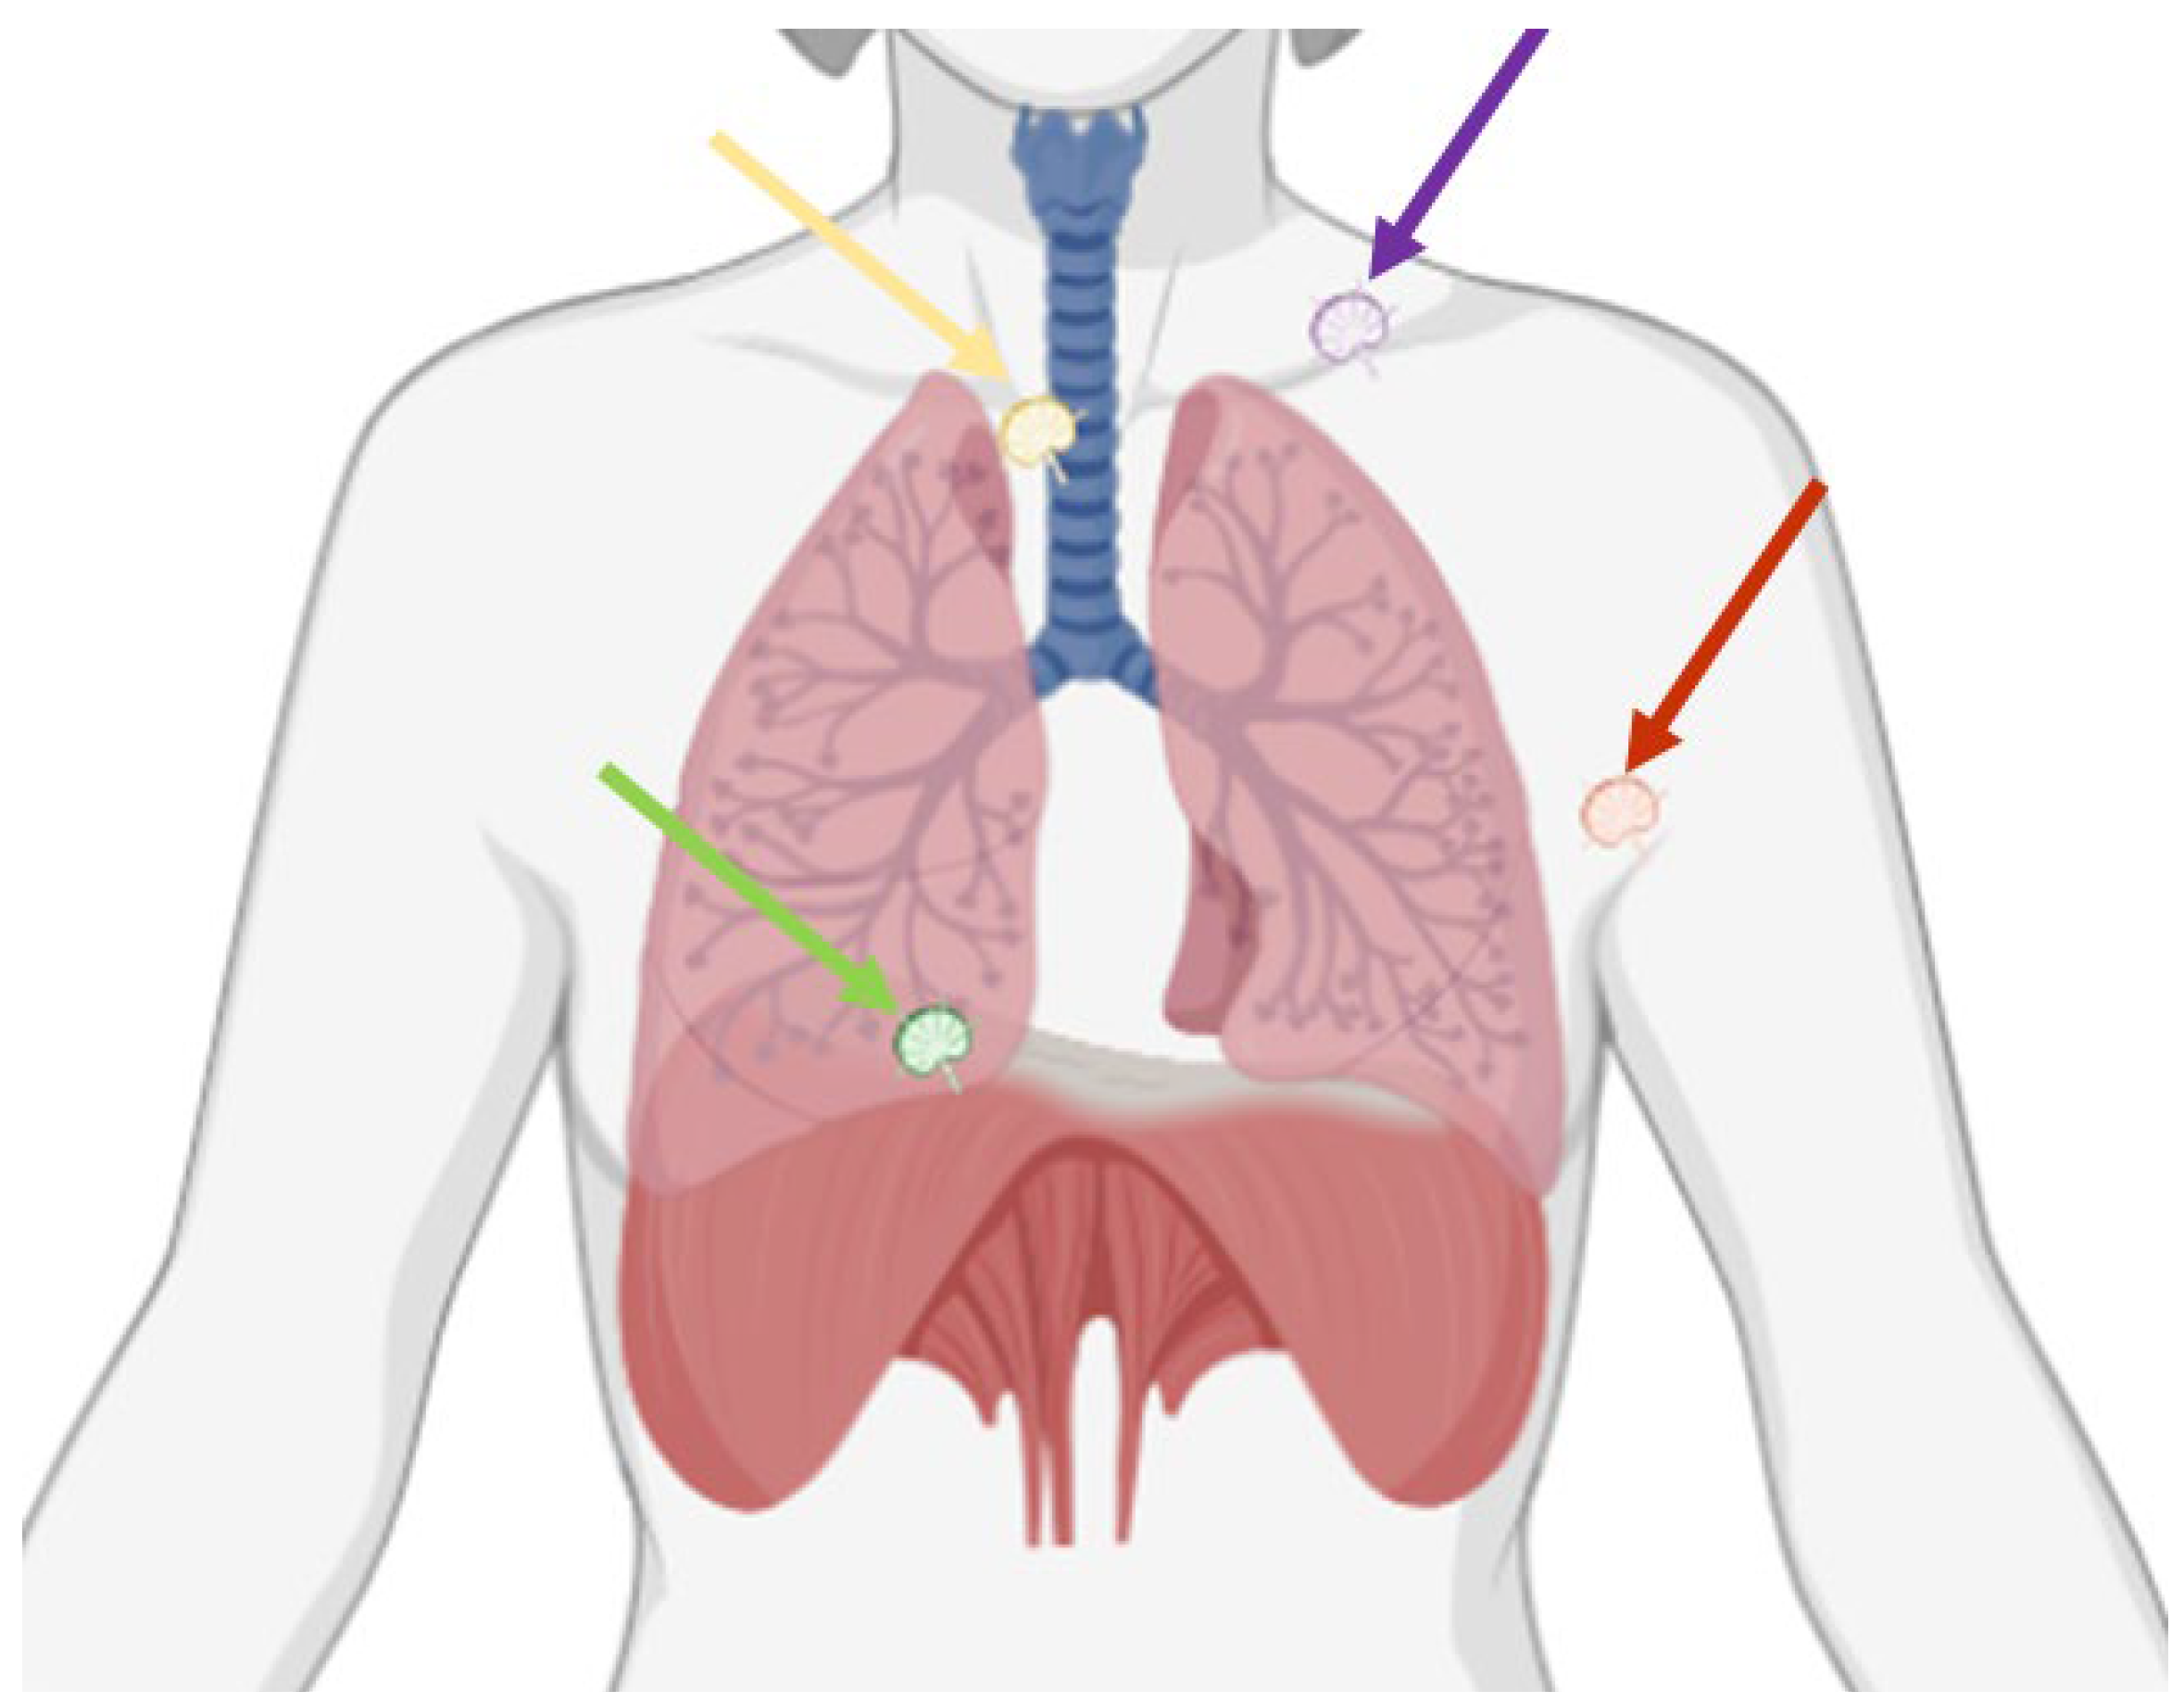

Indeed, close multidisciplinary collaborations and advancements in imaging and surgical techniques may allow selected, previously deemed inoperable, stage IV disease patients to be considered for complete cytoreductive surgery. Therefore, the goal of this paper is to review the anatomy, imaging, and surgical techniques of extra-abdominal lymphadenopathies in OC patients (Figure 1), with a specific focus on the diagnosis and surgical resection of lymphadenopathies located in the supraclavicular fossa, in the axilla, in the mediastinum, and in the pericardiophrenic fat (Table 1).

Figure 1.

Possible thoracic sites of lymphadenopathies in ovarian cancer are the supraclavicular fossa (purple arrow), the axilla (red arrow), the mediastinum (yellow arrow), and the pericardiophrenic fat (green arrow).